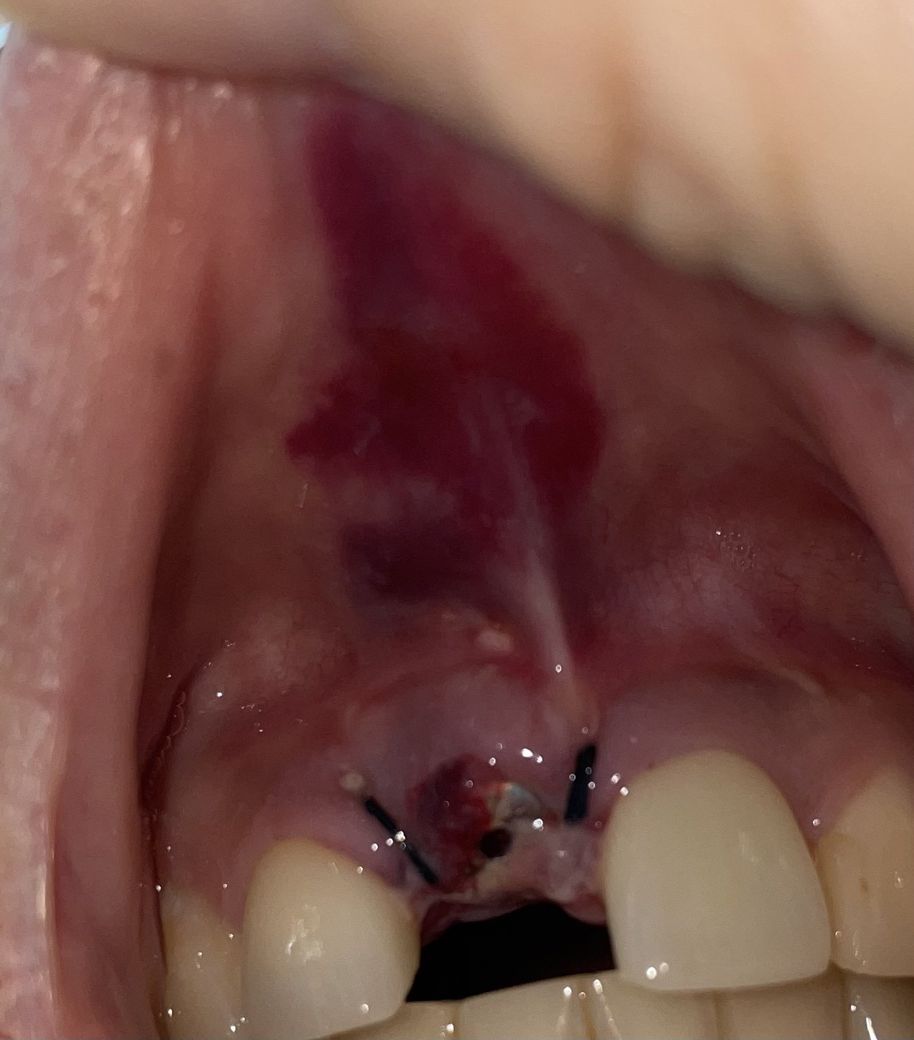

임플란트 식립 후 멍과 하얀물질

어제 오전에 앞니에 임플란트 식립하고

어제는 보철물이 깔끔하게 육안으로 보였는데

오늘 자고 일어나서 보니 하얀 막 같은 게

보철물을 둘러싸고 있어서요

사진에서 보이는 것처럼 멍이 많이 들었는데

• 1번 째 사진

현재 회복되는데는 큰 문제가 없어 보입니다. 잇몸이 회복되는 과정에서 섬유화가 진행되면 지금과 같이 하얗게 변화하거나 일부 막이 생길 수 있습니다. 또한 시술 당시의 트라우마로 인하여 지금과 같은 출혈 양상은 나타날 수 있습니다. 다만 사진을 찍기 위해 잇몸을 과도하게 올리는 등의 행위를 하는 것이 오히려 더 안 좋은 영향을 끼치게 됩니다. 따라서 회복되기 전에는 주위 조직을 건드리지 않는 것이 좋습니다.

• 하얀막은 잇몸이 치유되는 조직으로 보입니다.

• 부기가 가라앉고 빠지면서 멍이 발생이 될 수 있습니다. 일반적으로 시간이 경과하면서 자연치유됩니다.

하얀막 같은 것은 잇몸점막에 생기는 일종의 딱지라고 보시면 되며 정상적인 치유 과정입니다.

그래도 두면 저절로 없어집니다. 윗쪽에 붉게 보이는 것은 점막에 멍이 든 것입니다.

이것 또한 붓기가 빠지면 정상적인 칼라로 돌아옵니다.

사진으로밨을때 주위가 부어있고 위막이 덮어져있습니다. 자연스러운 현상입니다.